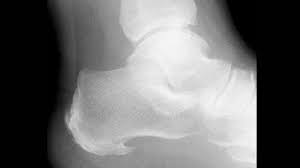

Nov 13, 2019 · if you feel pain in your heel, you might think you have a heel spur. Healthprep.com has been visited by 100k+ users in the past month Point of tenderness at the bottom of the heel that makes it hard to walk barefoot. See full list on wikihow.com However, only 50% of people who have heel spurs actually feel any pain because of it. What are the symptoms of heel spurs? Kuru® heel spur shoes mold to feet. Aug 28, 2020 · a heel spur is a calcium deposit causing a bony protrusion on the underside of the heel bone.

See full list on wikihow.com These symptoms may spread to the arch of your foot. There are three main parts of your foot's anatomy: Aug 28, 2020 · a heel spur is a calcium deposit causing a bony protrusion on the underside of the heel bone. If the pain is on the bottom of the heel, plantar fasciitis is most likely the reason.